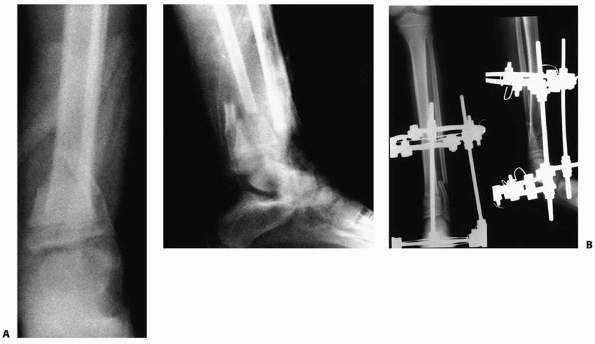

FIGURE 25-26 A.

Anteroposterior and lateral radiographs of the tibia of a 12-year-old boy who was struck by a car. This child sustained a grade IIIB open middle one third tibial fracture, a Salter-Harris type II fracture of the distal tibial physis with associated distal fibular fracture (closed arrows), and a tibial eminence fracture (open arrow). B. Irrigation and débridement and application of an external fixation device were performed. C. The fracture of distal tibial physis was stabilized with a supplemental pin attached to the external fixation device. Open reduction and internal fixation of the fibula was performed to enhance the stability of the external fixator in the distal tibia. D. Anteroposterior and lateral radiogrphs of the tibia approximately 9 months after injury demonstrate healing of the tibial eminence fracture, the comminuted middle one third tibial fracture, and the distal tibial physeal fracture. The distal tibial physis remains open at this time. |

FIGURE 25-27 A. Anteroposterior and lateral radiographs of a grade IIIB open fracture of the distal tibia and fibula. B.

Anteroposterior and lateral radiographs after fracture reduction and stabilization with an Ilizarov circular fixation frame. (From Sharps CH, Cardea JA. Fractures in the shaft of the tibia and fibula. In: MacEwen GD, Kasser J, Heinrich SD, eds. Pediatric Fractures: A Practical Approach to Assessment and Treatment. Baltimore: Williams & Wilkins, 1993:325, with permission.) |